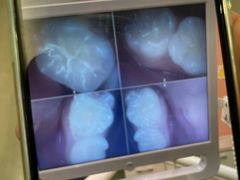

• 牙博士口腔品牌连锁(杨浦店)

• -牙博士口腔品牌连锁(杨浦店)

刘薇 | 21-10-28